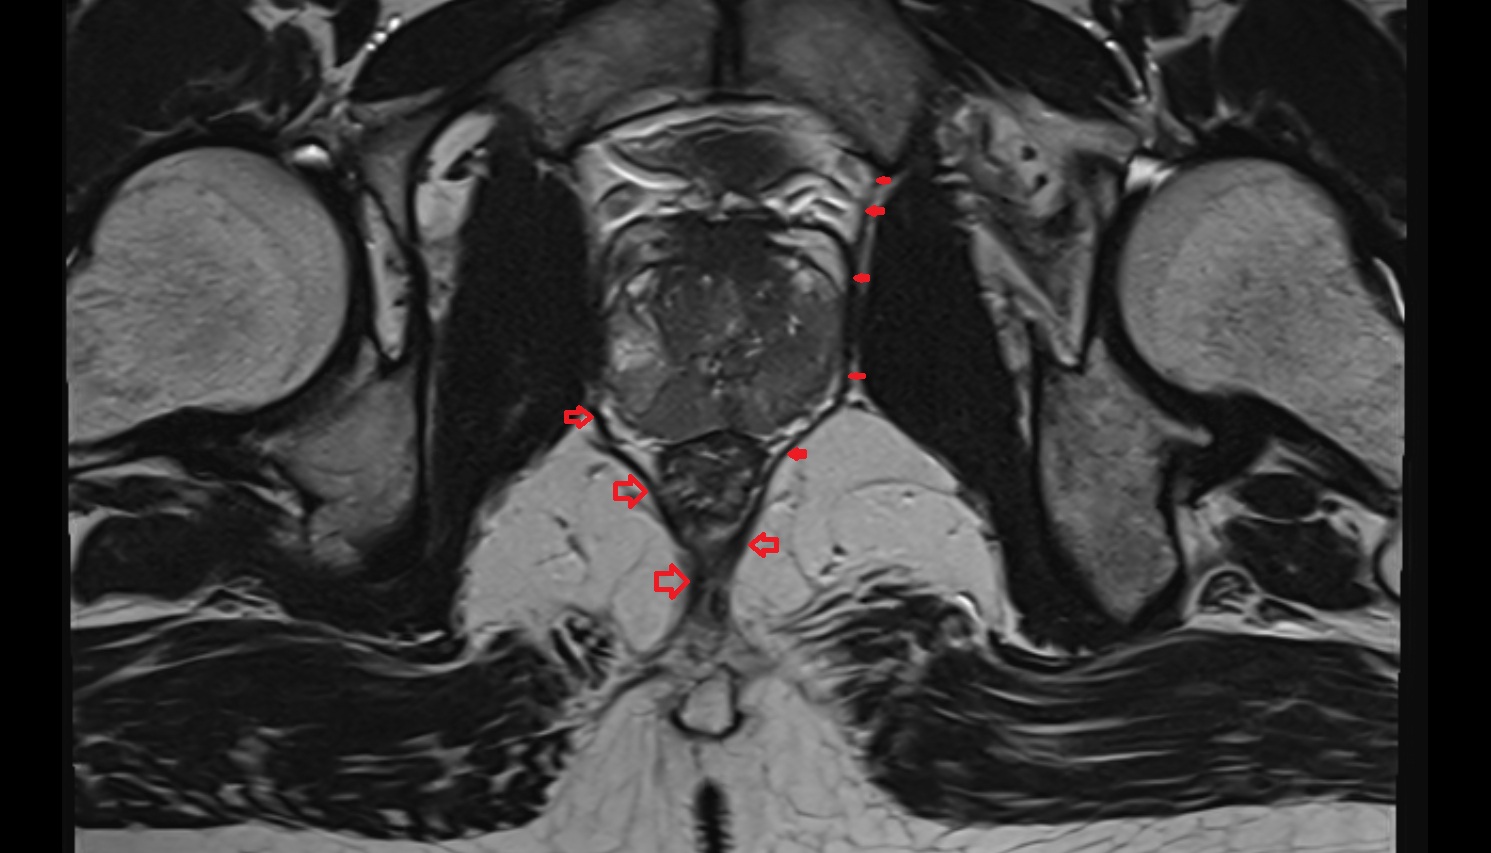

- Peripheral zone of prostate

- Anterior Fibromuscular Stroma of prostate

- Central zone of prostate

- Transitional zone of prostate